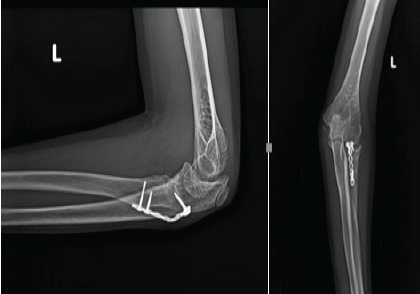

Flexor Carpi Radialis Tendon Stabilization for Chronic First Carpometacarpal Joint Instability: Clinical Outcomes from a Case Report

Akshay Punekar , Santosh D Ghoti , Mohammed Amjad Sohiel , Niranjan Sunil Ghag , Alok Yadav , Aditya A Agarwal